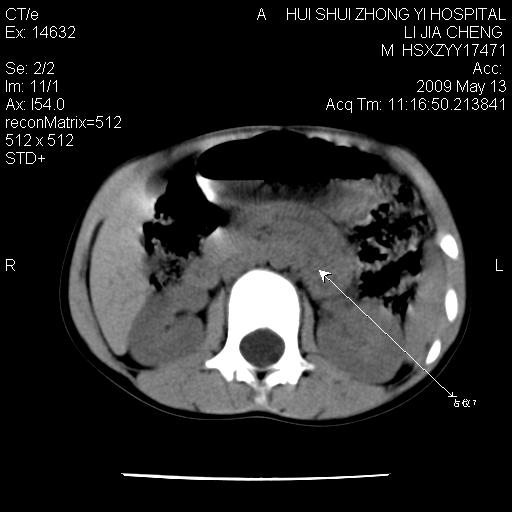

标题: PED1887:男性,6岁。反复脐周疼痛2年余。请各位老师看下腹 [打印本页]

标题: PED1887:男性,6岁。反复脐周疼痛2年余。请各位老师看下腹

该患者可自行好转,大小便未见异常,化验:便未见虫卵,血常规:wbc:8000;淋巴3600,中性45%

脂肪肉瘤可能性大,大血管边界不清,特别是腔静脉。不除外其他腹膜后肿瘤。

是不是有蛔虫哦,楼主图示块影前方肠管壁显著增厚,不除外慢性肠炎或肠壁占位,建议肠道准备后复查

肠道准备不足,im15---------------------18左侧腹腔病变?

来源于十二指肠水平部病变?建议行进一步检查。

肠管管壁均匀增厚,炎性可能

考虑腹疝可能。

是小肠,壁稍厚可能是肠腔未很好充盈所致,腹部ct扫描未见明显异常。